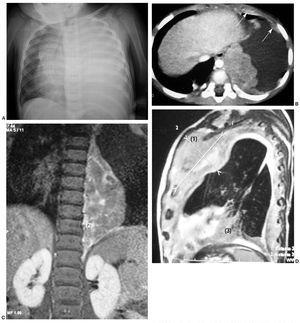

Presentamos el caso de un niño de 20 meses con antecedentes de prematuridad y enfermedad de membrana hialina, que comienza con disnea y mal estado general. En la radiografía torácica se observa una opacificación del hemitórax izquierdo por derrame pleural masivo (fig. 3A). Tras realizar un drenaje pleural se extraen 500 ml de líquido hemático. Se le realiza una TC en la que se observa una gran masa torácica paravertebral izquierda, sólida, polilobulada, con extensión desde D3 a D10, y con semiología radiológica de lesión extrapulmonar que depende fundamentalmente de la pleura. Presenta un patrón de captación discreto y homogéneo, y no muestra signos de afectación del canal raquídeo ni de la pared torácica (fig. 3B). Se realiza biopsia de la lesión con diagnóstico histológico de tumor de células azules, redondas y pequeñas, con diferenciación muscular, compatible con BPP tipo III. La evolución es tórpida, a pesar del tratamiento con quimioterapia y tres intervenciones quirúrgicas. En la RM de control se observa un engrosamiento pleural difuso metastásico en el hemitórax izquierdo (figs. 3C y 3D). La afectación tumoral prosigue, presentando finalmente un colapso pulmonar, invasión mediastínica y de pared torácica anterior, metástasis orbitarias y diseminación abdominal. Fallece a los dos años del diagnóstico.

Fig. 3. Caso 3. (A) Radiografía inicial. Derrame pleural izquierdo masivo y desplazamiento mediastínico contralateral. (B) Tomografía computarizada de tórax con contraste tras drenaje del derrame pleural; corte axial. Masa extrapulmonar paravertebral izquierda, dependiente de pleura, con lesiones nodulares en cavidad pleural (flechas) y sin extensión al canal medular ni afectación de pared costal. Resonancia magnética en secuencias T1 + Gd (C) y T2 (D). Engrosamiento pleural difuso metástasico en el hemitórax izquierdo con varias masas, una en el ápex pulmonar izquierdo con extensión al mediastino anterosuperior y que abomba la pared torácica anterior (1), otra paravertebral izquierda (2) y la tercera en el seno costofrénico anterior izquierdo (3).